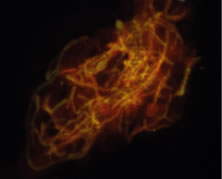

The preferred stains for identification of hyphal fragments and yeasts in smears of corneal scrapings are acridine orange and calcofluor white.33, 34, 35, 36, 37, 38 Each of these techniques requires use of a fluorescent microscope. The optical activity of acridine orange is due to the binding of the dye to deoxyribonucleic acid (DNA) of bacteria, fungi, and amoebae to form a green-fluorescing complex. Acridine orange is more sensitive than the Gram stain in detecting microorganisms in clinical specimens36 and is, therefore, a rapid and sensitive method for screening all corneal smears in suspected infectious keratitis. If microorganisms are detected by acridine orange stain, the slide can be washed and stained with Gram or other specific stains. The preferred procedure is to fix the smears in 95% methanol for 5 to 10 minutes, apply the acridine orange dye (number 3336-75)* for 2 minutes, rinse the slide with tap water, blot dry, and examine by fluorescent microscopy. Hyphal fragments stain yellow-orange or green, and yeasts stain brilliant orange (Fig. 22).

Fig. 22. Curvularia senagalensis keratitis. Fluorescent microscopy. Direct smear of corneal scraping stained with acridine orange. Note the distinction of the septate hyphal fragments. (× 630.)